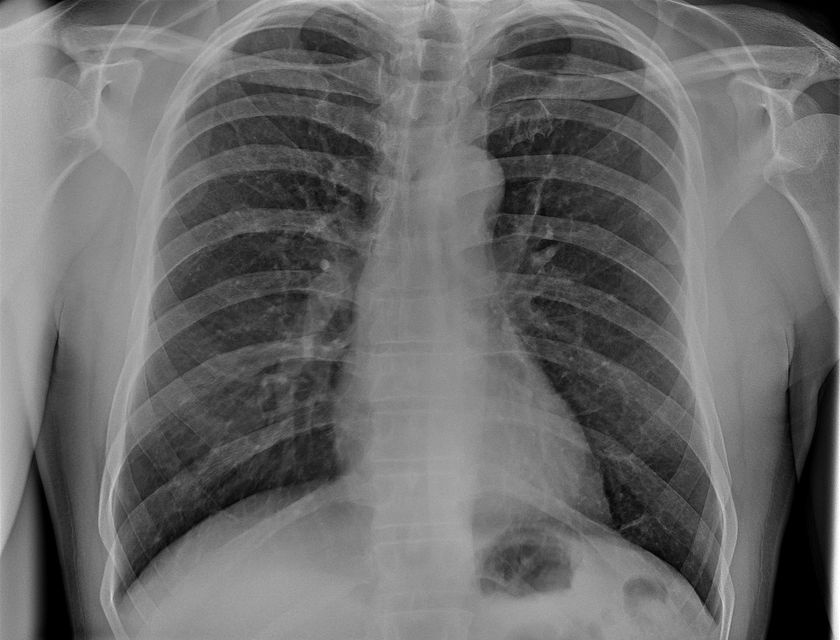

画像4

TRB 9020Hで撮影した胸部レントゲン写真

※90 kV HP mode, 1.65 mAs, 0.06 sec